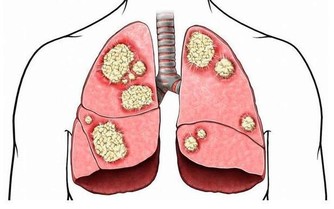

常言道,生命在於運動。簡單來講,日常中適當鍛煉是十分有益健康的,有利於增強體質,改善三高,對於保護血管也有良好作用。那麼,每天走多少步,可以保護血管?日常做什麼可以預防血管硬化?

每天走6千步,能有效保護血管

世界衛生組織曾提出,每個人每天應做30分鐘左右的有氧運動;而根據我國國民身體狀況,每天走大概6千步,就有助於保護血管。

如果是選擇慢跑、騎車等運動,則最好鍛煉到稍微流汗為宜。因為出汗能夠排出體內的垃圾,如尿酸、乳酸等;在這一過程中,人體溫度還會降低,而體溫一升一降的時候,能夠讓體內血管的彈性提高。

日常保護血管,還可以做什麼?

1、避免長期熬夜

熬夜時,人體會分泌很多激素,這類激素會收縮血管,導致血液流動受阻,血液粘稠度提高,進而損傷血管。因此,日常保護血管,需避免經常熬夜,最好在晚上十一點前就睡覺。

2、保持良好情緒

長期處於憤怒、焦躁等負面情緒中,也會影響血液循環,損害血管,更甚者引起心腦血管疾病。所以,平時一定要調節好心態,保持良好情緒。

3、遠離菸酒

想要保護血管,還要注意遠離菸酒。因為香煙包含大量尼古丁、焦油等有害物質,進入血液會阻礙脂肪代謝,造成血管彈性下降;而長期酗酒,同樣會加大患心血管疾病的風險。

4、多吃能軟化血管的食物

在飲食方面,建議均衡營養,多吃新鮮的瓜果蔬菜,少吃高糖高鹽高脂食物。另外,也不妨多吃能夠軟化血管的食物。